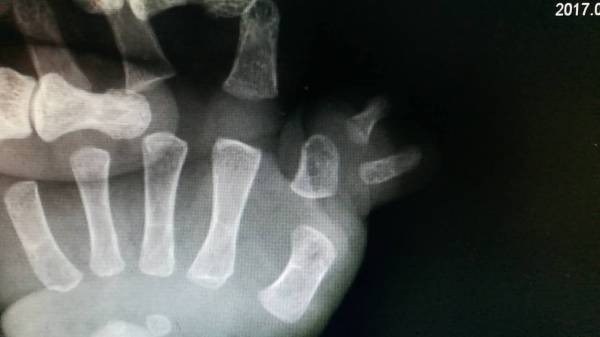

明天准备手术小孩

双手复拇畸形

微信图片_20170427164904.jpg

微信图片_20170427164908.jpg